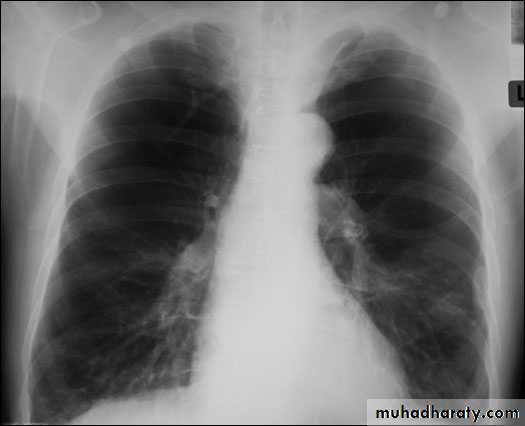

Radiology

Chest x-rayHyperlucency

Vascular attenuationHyperinflation (emphysema).

EmphysemaCT scan in Emphysema

Chronic obstructive bronchitis